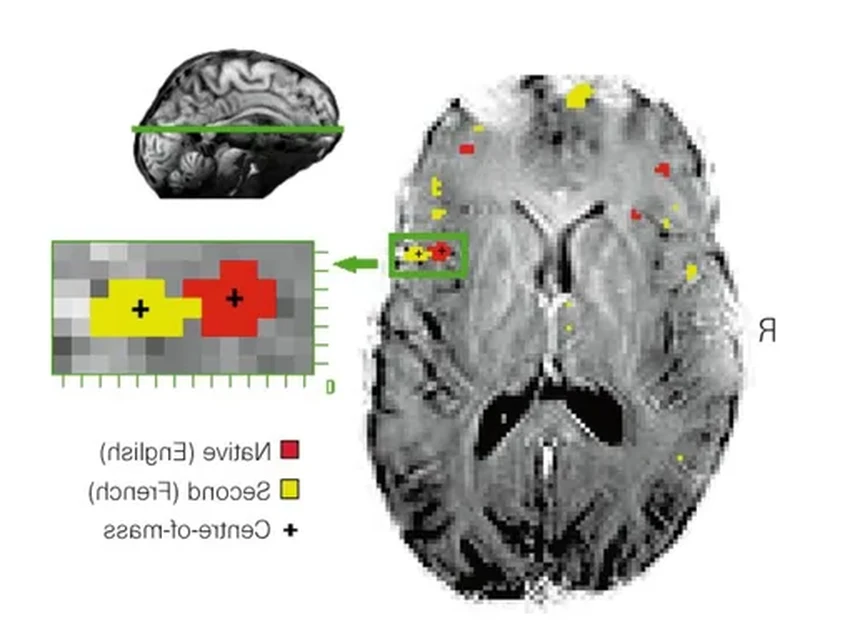

Самое удивительное открылось, когда ученые начали анализировать данные с электродов. Раньше, используя неинвазивные методы вроде фМРТ, нейробиологи приходили к выводу, что разные языки активируют разные участки мозга. Но прямой доступ к нейронам всё перевернул с ног на голову.

Оказалось, что когда Панчо думает на испанском или английском, основные всплески активности происходят в одном и том же речевом центре. Более того, паттерны его мозговой активности удивительно похожи на те, что наблюдаются у людей, выросших с двумя языками с детства.